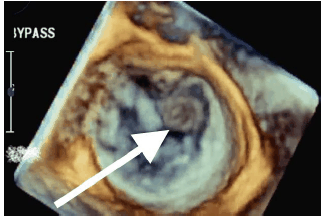

Homem de 65 anos, internado devido ataque isquêmico transitórico, submetido a ecocardiograma transesofágico 3D para pesquisa de fonte emboligênica diagnosticando fibroelastoma papilar (seta).

Identifique em que scallop está localizada a patologia demonstrada pela seta.